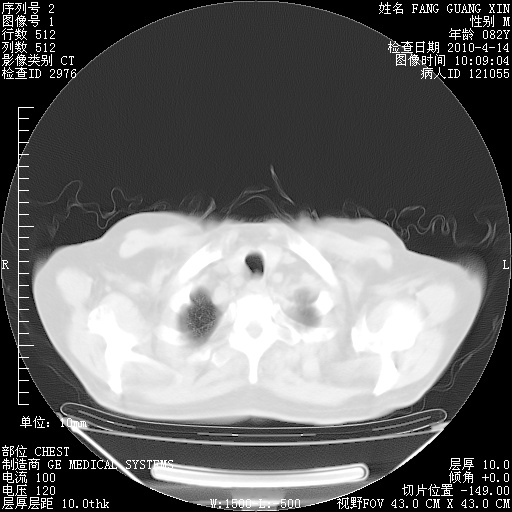

4月14日肺部CT

23.JPG

24.JPG

25.JPG

26.JPG

肺部CT平扫未见异常。